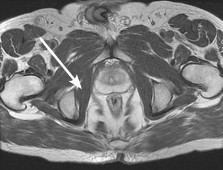

A 55-year-old woman feels a 'pop' in the back of her knee while squatting. An MRI is shown:

A posterior horn medial meniscus root tear is identified. Biomechanically, a complete medial meniscus posterior root tear alters contact pressures to a degree equivalent to which of the following?

Explanation

A complete posterior root tear of the medial meniscus leads to a complete loss of hoop stresses, resulting in meniscal extrusion. Biomechanically, this alters peak tibiofemoral contact pressures and reduces contact area to a degree equivalent to a total meniscectomy, leading to rapid articular cartilage degeneration.